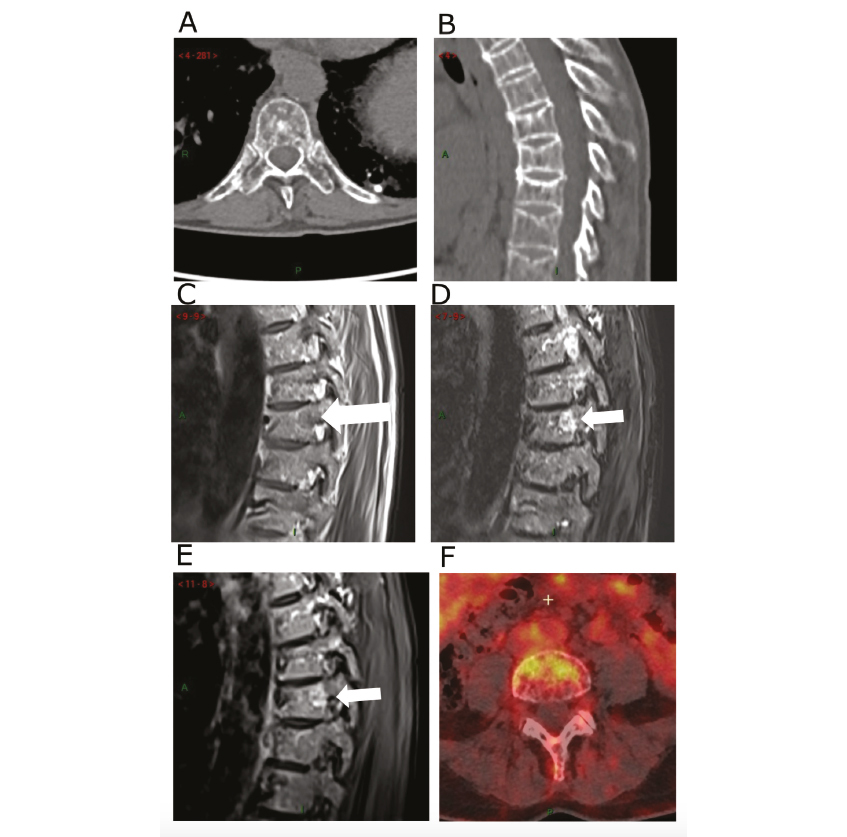

Figure 2. Bilan d'imagerie au diagnostic du myélome

(A-B) Scanner low dose non injecté du rachis thoraco-lombaire retrouvant une déminéralisation avec une trame osseuse hétérogène micro lacunaire au niveau lombaire (A) et des tassements vertébraux thoraciques (B) par insuffisance osseuse dans le cadre de l'ostéoporose. (C-E) IRM du rachis thoracique retrouvant une lésion focale de 8mm au niveau T8 (flèche) avec un hyposignal T1(C), un hypersignal après injection de gadolinium (D) et en séquence STIR (E). (F) TEP-scanner au 18-FDG retrouvant une fixation hypermétabolique avec SUV 4,6 d'une lésion du rachis lombaire.